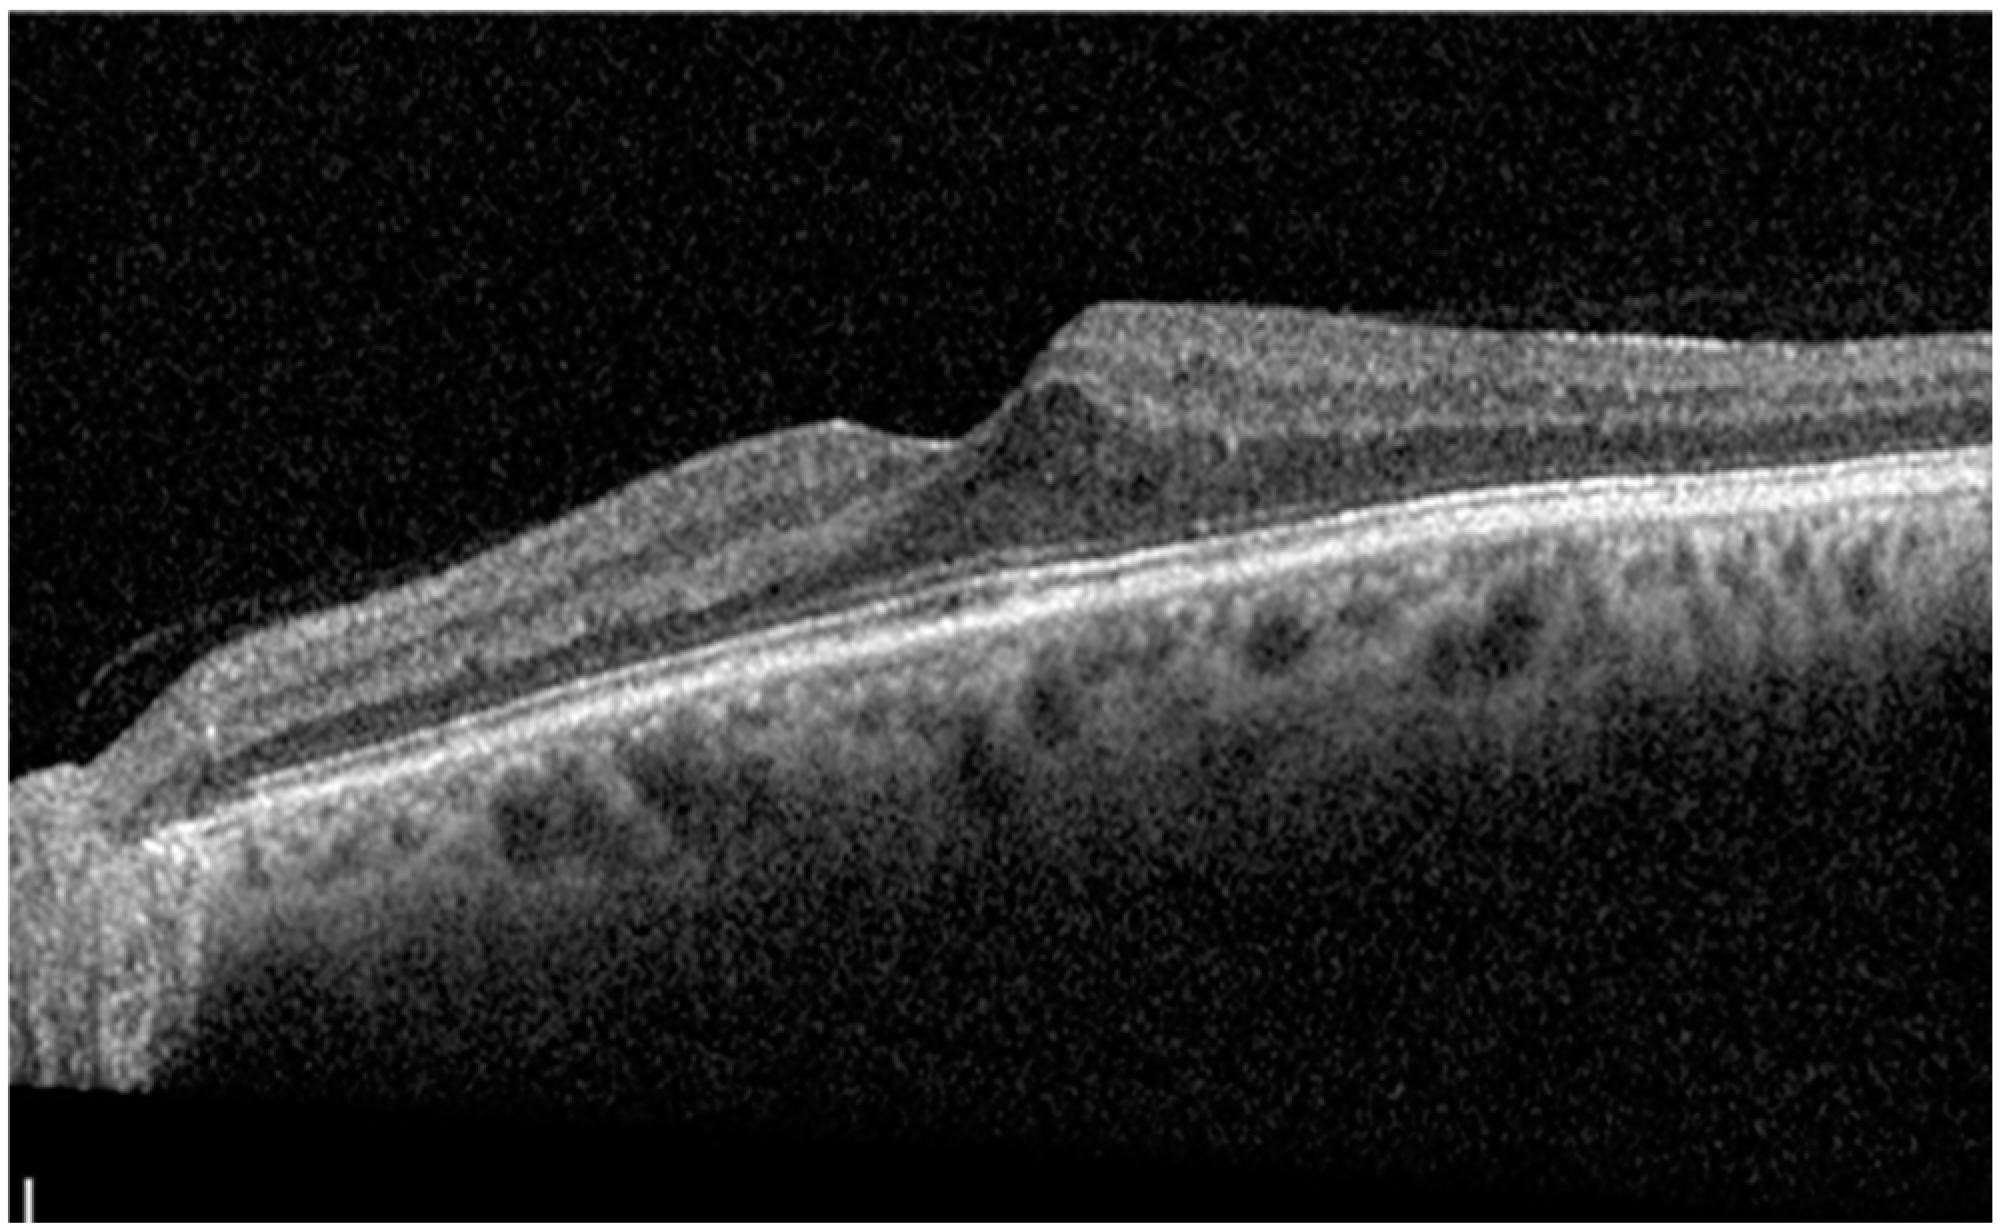

| Central Subfield Thickness, µm (mean ± SD) | 496.93 ± 79.06 | 379.93 ± 116.96 | 0.0001 | 353.53 ± 116.11 | 0.0081 | 334.73 ± 111.99 | 0.0017 | 318.47 ± 99.58 | 0.0073 | 300.67 ± 84.61 | 0.0017 |

| Subfoveal Choroidal Thickness, µm (mean ± SD) | 188.6 ± 84.67 | 182.07 ± 89.60 | 0.2842 | 176.40 ± 83.25 | 0.1966 | 182.33 ± 80.70 | 0.2501 | 179.20 ± 81.26 | 0.1717 | 179.20 ± 81.83 | 0.1718 |